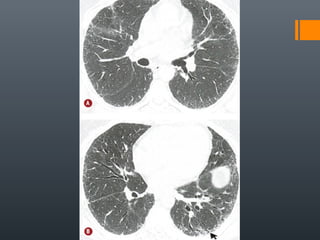

O documento discute vários conceitos radiológicos incluindo consolidação, atelectasia, nódulos, pseudocavidades e padrões intersticiais, fornecendo definições, sinais e diagnósticos diferenciais para cada tópico. Ele também discute a redução da atenuação pulmonar e fornece um link para mais informações.